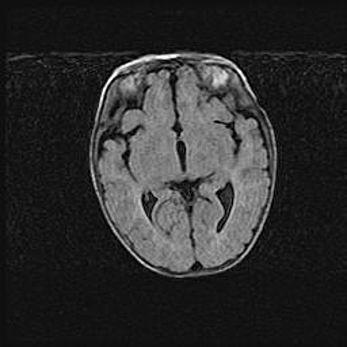

Сообщающаяся гидроцефалия. Кистозная энцефаломаляция головного мозга.

Возраст: 3 месяца 4 дня

Вес: 3100 г

Пол: женский

Окружность головы: 34 см

Срок гестации: 31 неделя

Кистозная энцефаломаляция головного мозга - одна из форм поражения головного мозга в детском возрасте. Характеризуется возникновением множественных и распространённых кист в коре, белом веществе и подкорковых образованиях головного мозга у плодов, новорождённых и детей раннего возраста. Развитие кистозной энцефаломаляции связано с внутриутробной асфиксией и гипотонией, родовой травмой, тромбозом синусов, пороками развития сосудов, инфекциями, сепсисом и другими причинами. Наиболее значимые инфекционные агенты: вирусы простого герпеса, цитомегалии, краснухи, токсоплазмы, энтеробактерии, золотистый стафилококк и другие.